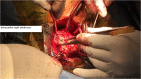

Primary cardiac tumour is a rare entity as secondaries in the heart are more common. A 2-year-old child was having repeated respiratory tract infection with poor oral intake and poor activity for 3 months. His symptoms progressed from New York Heart Association (NYHA) Class II to IV. On evaluation he had an intracardiac mass with extracardiac extension. Emergency tumour excision under deep hypothermic circulatory arrest was performed with provisional diagnosis of sarcoma. But Serum markers, histopathological examination and immunohistochemistry confirmed diagnosis of yolk sac tumour. Postoperative recovery was uneventful and the child was receiving adjuvant chemotherapy. Extensive literature review revealed only four cases of primary intracardiac yolk sac tumour published till date. Our case report is unique, in that intracardiac tumour had extracardiac extension by infiltration through right atrial wall. Previous four reports mention purely intracardiac mass.